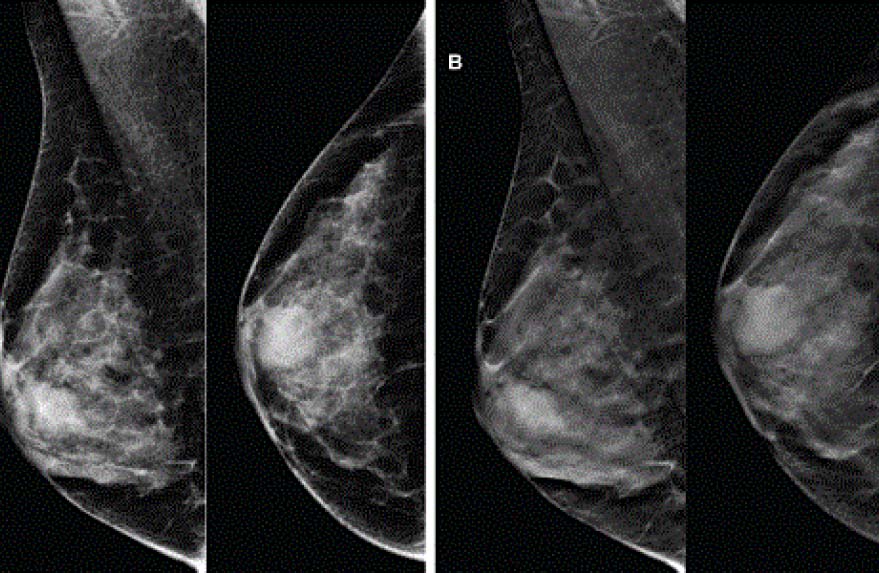

Nhũ ảnh là kỹ thuật chụp X- QUang tuyến vú để sàng lọc ung thư vú đặc biệt phát hiện các vi vôi, xáo trộn cấu trúc mà việc thăm khám thông thường không phát hiện được.

- Chụp 3D với độ nét, độ tương phản cao, chi tiết vượt trội cho phép thấy rõ vị trí và giới hạn tổn thương mà trên X-Quang vú thông thường không thấy rõ.

- Tăng tỷ lệ phát hiện ung thư vú lên đến 40% so với 2D, đồng thời giảm tỷ lệ dương tính giả xuống 15%, đặc biệt với các mô vú đặc và mô vú ở phụ nữ trẻ tuổi.